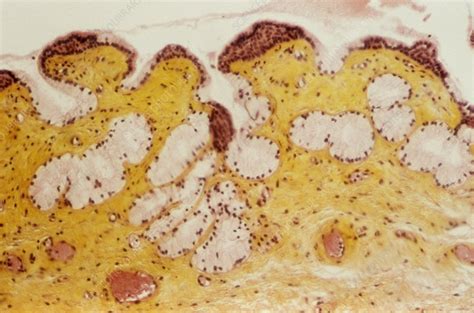

Before delving into the removal process, it’s essential to understand what Bartholin cysts are and how they form. These cysts occur when the ducts of the Bartholin glands become obstructed, causing the secreted fluid to accumulate and form a cyst. The blockage can be due to various reasons, including infection, injury, or simply a natural blockage without any underlying cause. While many Bartholin cysts are small and do not cause symptoms, larger cysts can lead to significant discomfort, pain during sexual intercourse, and difficulty walking or sitting.